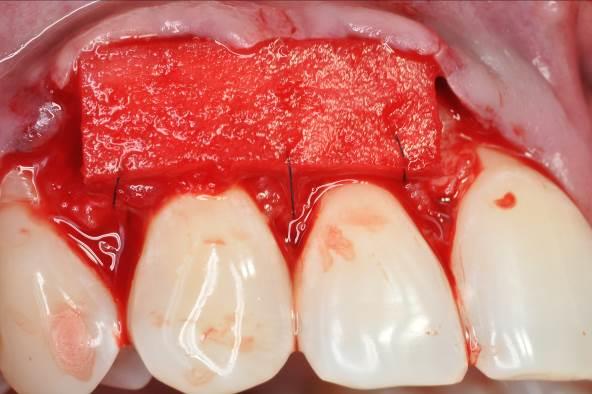

04/06 - Rehydrated mucoderm® placed over the root surfaces and sutured to the wound bed.Multiple gingival recessions treated with the modified coronally advanced flap in conjunction with mucoderm® and Straumann® Emdogain® - Dr. D. B. Hangyási